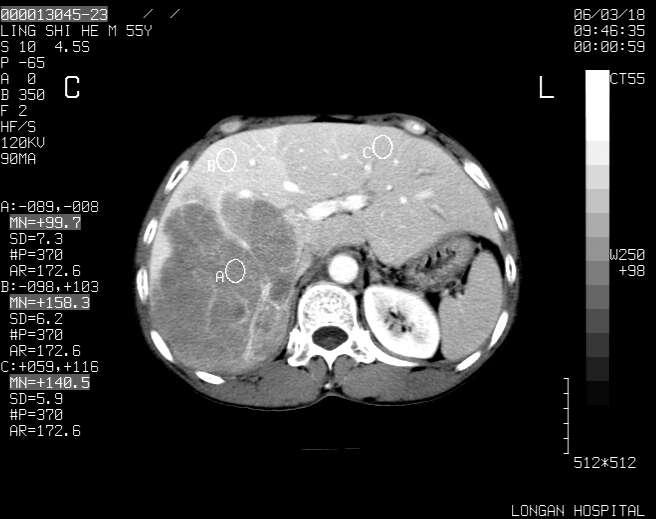

以下是引用guzhongliangddd在2006-3-21 22:13:00的发言:[br]病灶主要位于肝右叶的后份,内见异常血管,门脉主干及右支受侵{提示有癌栓形成},门腔间隙内见增大淋巴结。肝左叶内未见异常。

以下是引用zhuxinli在2006-3-22 1:23:00的发言:[br][br] 病灶主要位于肝右叶的后份,内见异常血管 .门脉右支截断,右叶前段早期强化(考虑动静脉漏),腹膜后肿大淋巴结,病灶逐渐强化,考虑为胆管细胞癌[br]